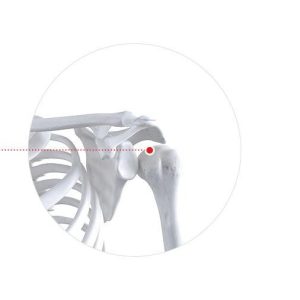

Мөрний үе мөрний гацалт, мултрал, эргэх булчингийн урагдал,мөрний үений шөрмөсний урагдал